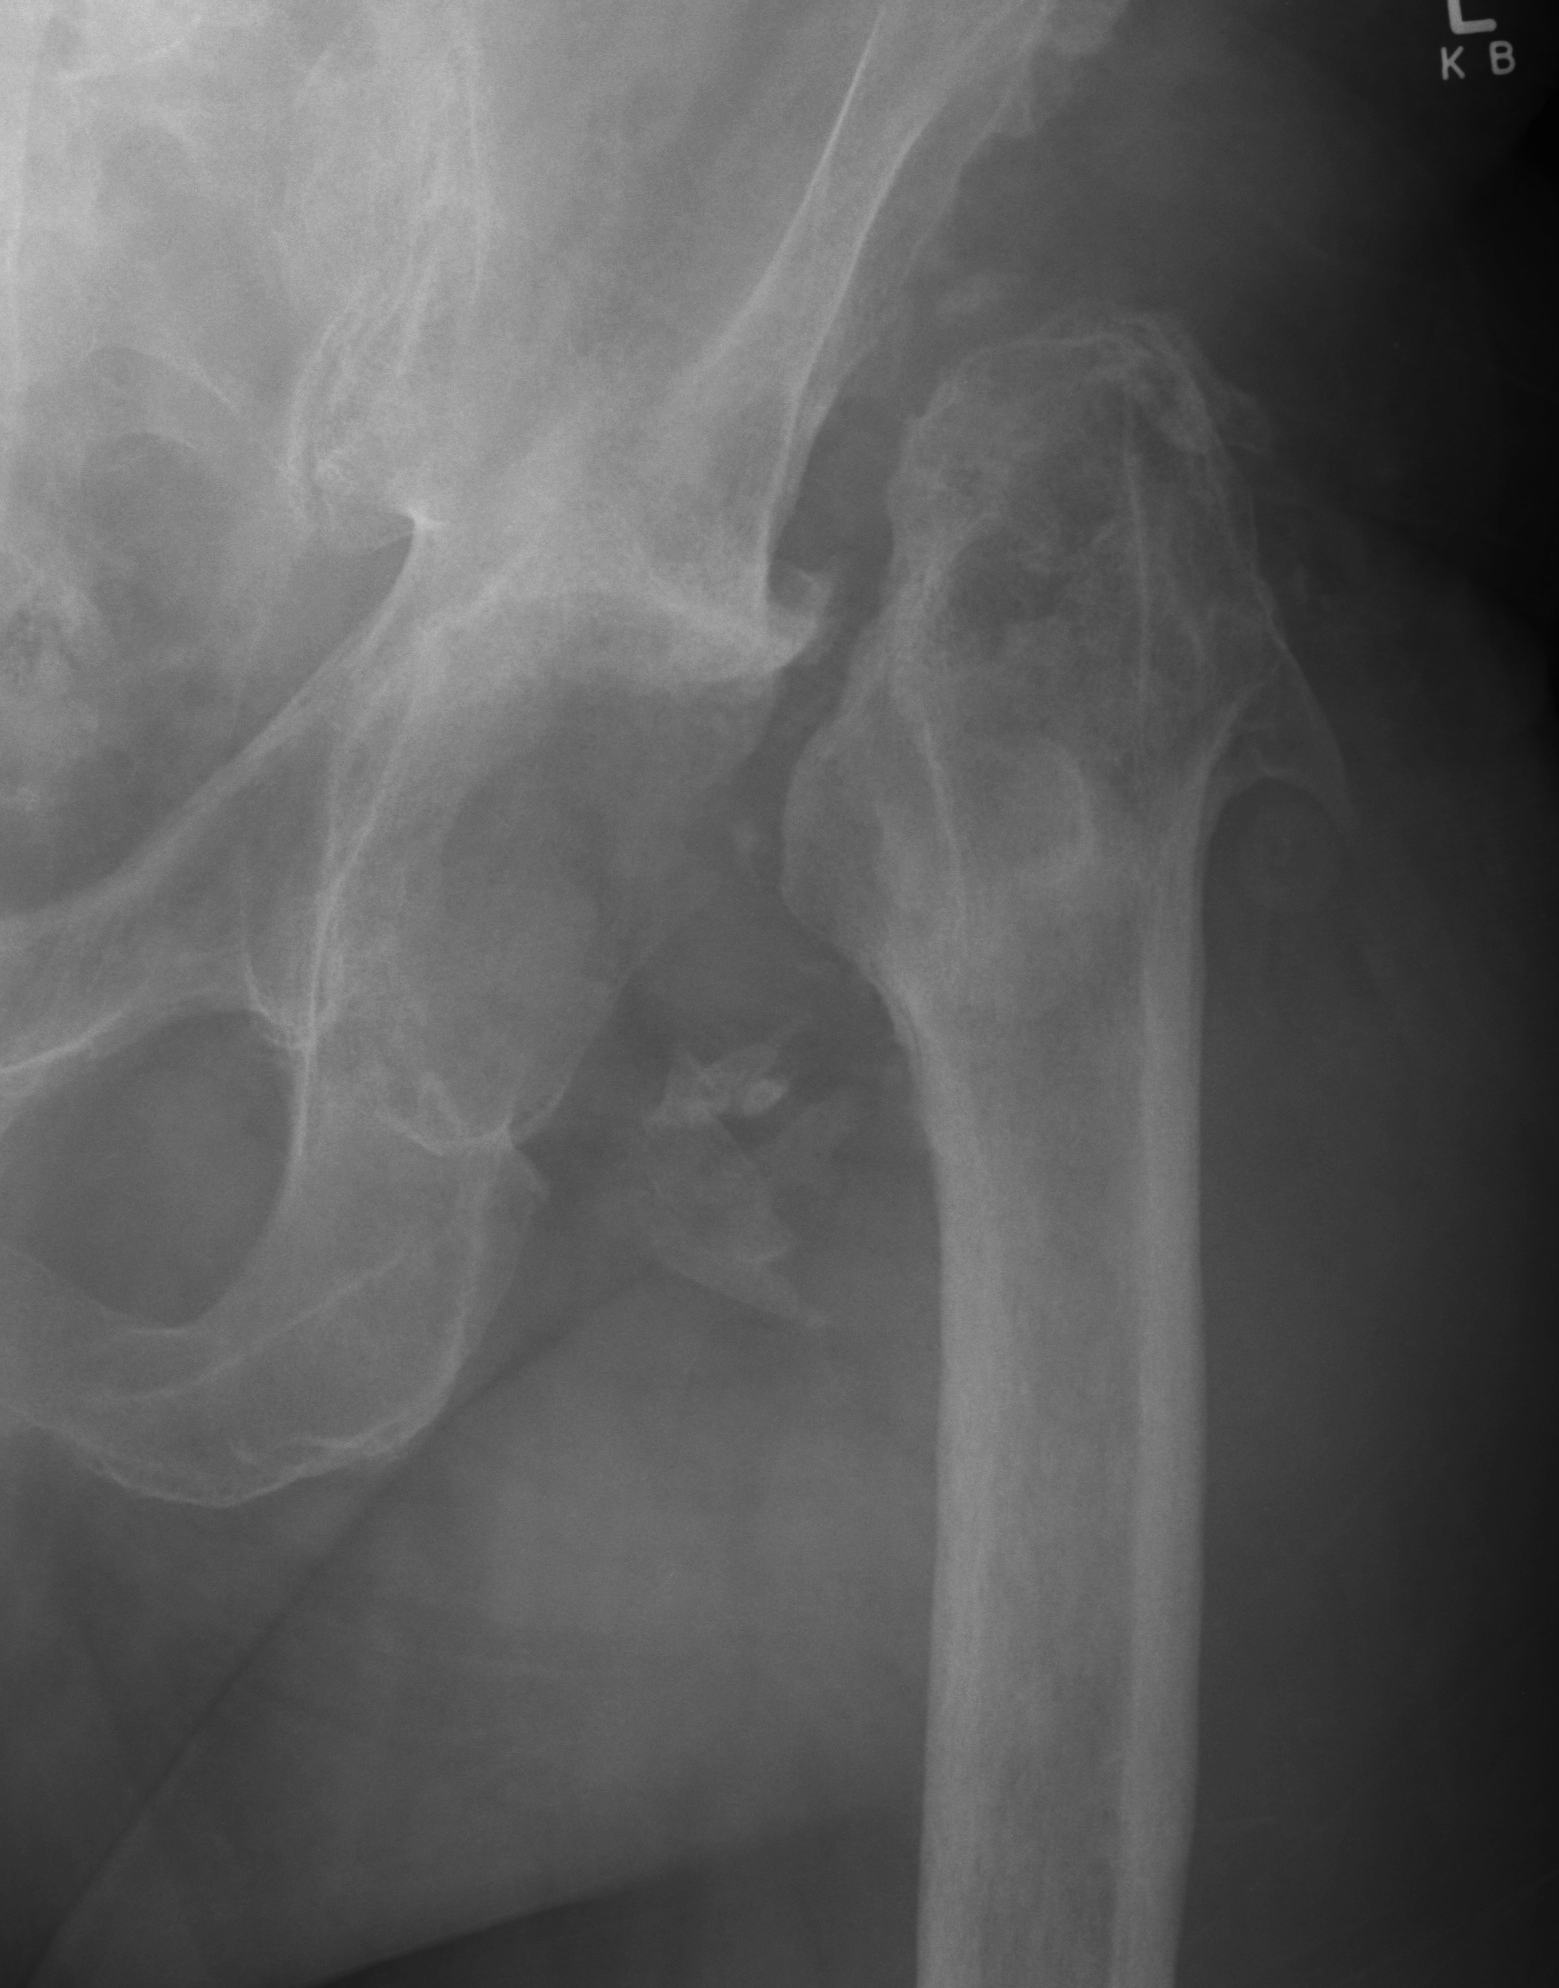

Resection Arthroplasty / Girdlestone

Indications

- medically unfit for further revision surgery

- refusal for further revision surgery

- sepsis control / virulent bug

- unrevisable due to bone loss

- unlikely to become mobile